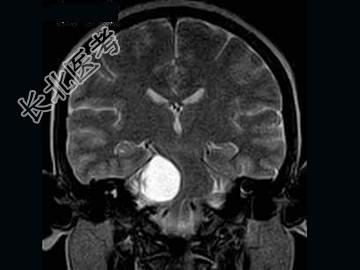

- 单项选择题女,41岁, 头痛,头晕, 走路不稳1个月余,MRI检查, 最可能的诊断为 ( )

A、听神经瘤

B、脑膜瘤

C、三叉神经瘤

D、胆脂瘤

E、神经纤维瘤